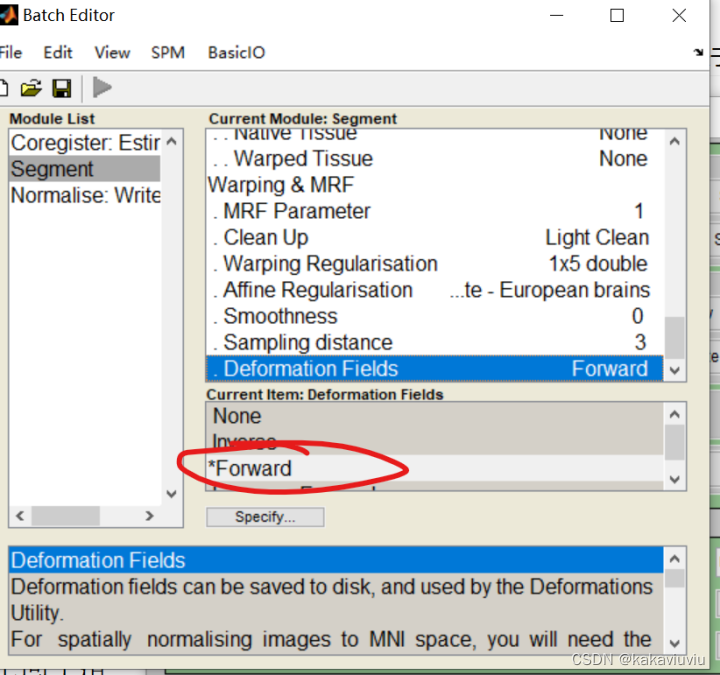

2.配准到个体fMRI的个体T1--->线性+非线性---->个体到标准空间的形变场(Segment)--形变场记录了卷纸是如何变成和抽纸一样形状的过程

然后点segment(也可以先选,之后来设置这些参数)